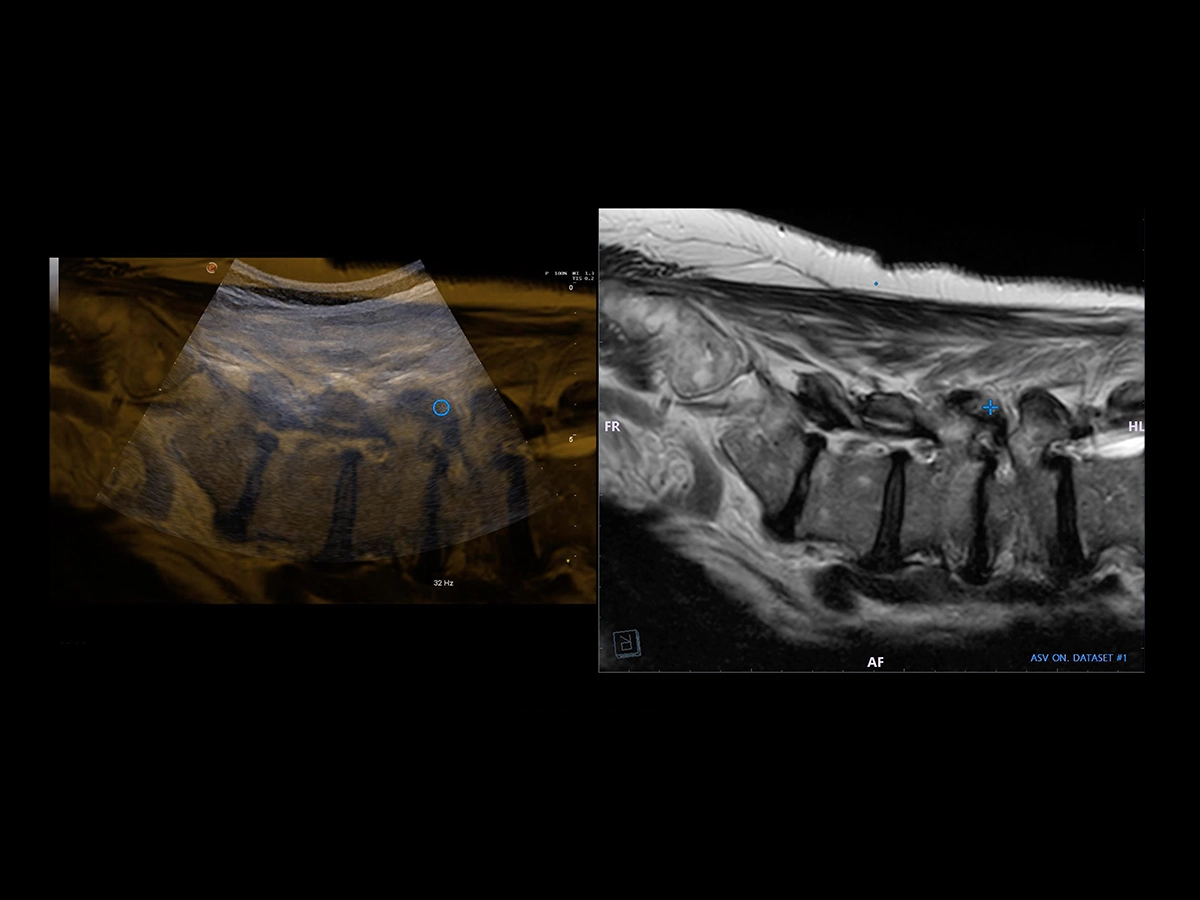

Virtual Navigator (VNav) is the Esaote technology for fusion imaging that enables US examiners to combine real-time ultrasound with datasets from second modalities to increase diagnostic accuracy and provide a more comprehensive understanding of a particular region of interest.

In Rheumatology, fusion imaging between CT/MRI and US can be particularly valuable in interventional procedures to increase the clinician’s confidence level.